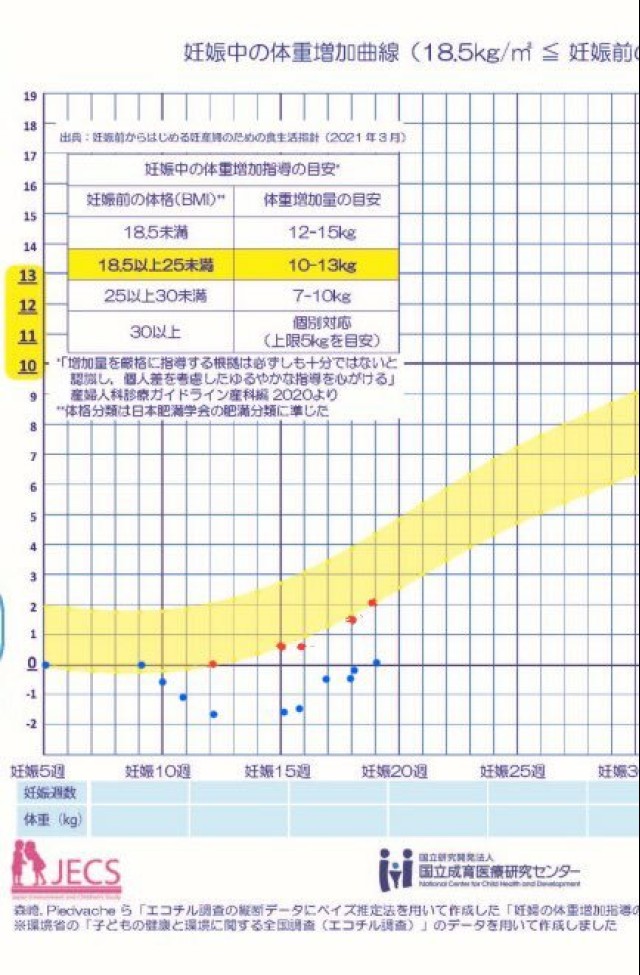

体重管理 妊娠前 つわり () GW () 今 () ※身長155cm GWで体重増えたと思ったら減った…? 食欲はあるけど食が細くなってしまったから量が食べれぬ。たんぱく質とっておけばOK??

体重管理 妊娠前体重からのシンプルな増減が青の点。 赤は、つわりでの最下限体重を0スタートにしたときの参考値✏️